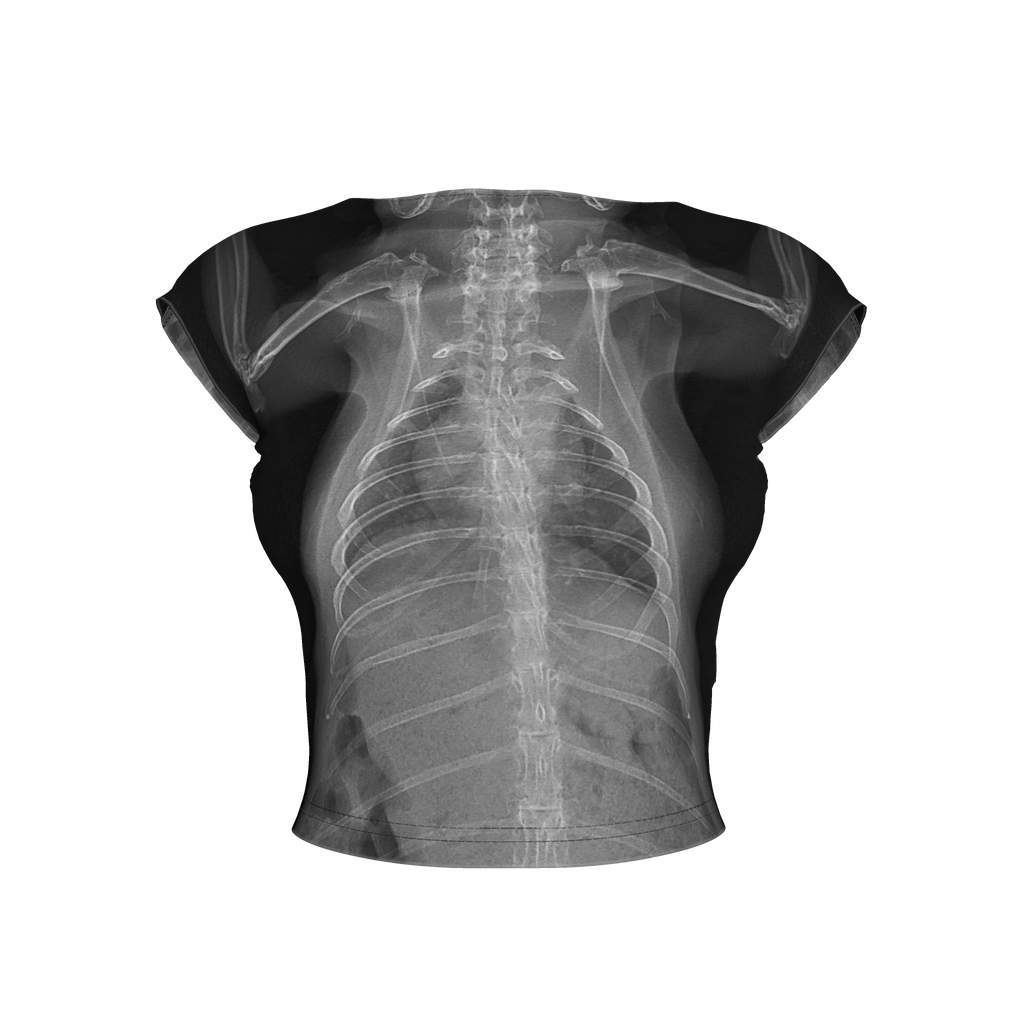

Toll of Love Backless Top

My pet rabbit had a health crisis earlier this year and needed intensive care. It was a long night at the hospital, but she is doing well. Her X-rays were a beautiful thing to come out of a horrible night and I made this outfit to transform those memories into something beautiful.